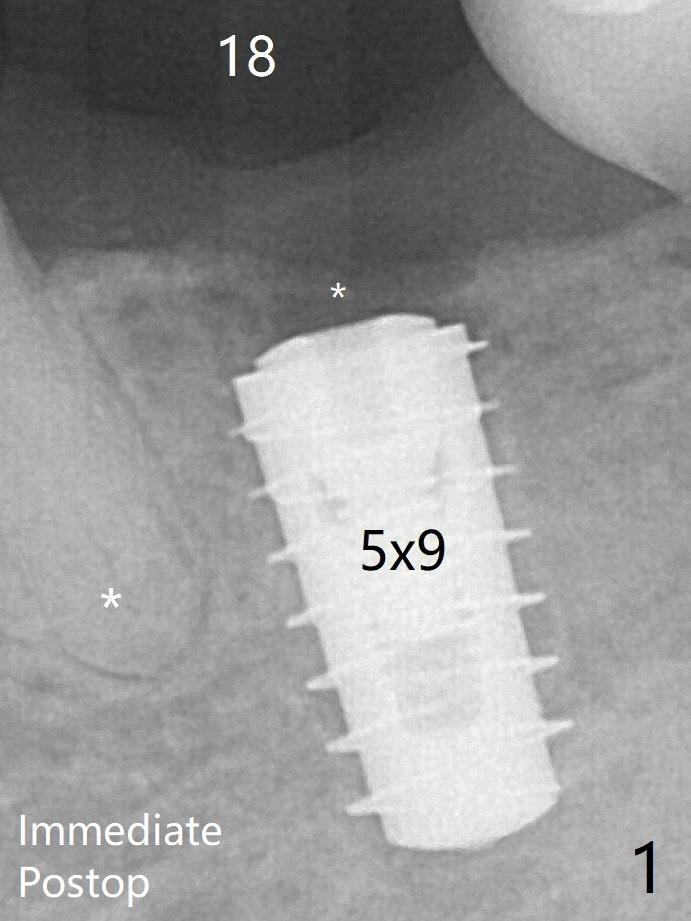

A layer of new bone forms on the top of the implant 3 months postop (Fig.4 *).  It will be removed with surgical handpiece and profile drill